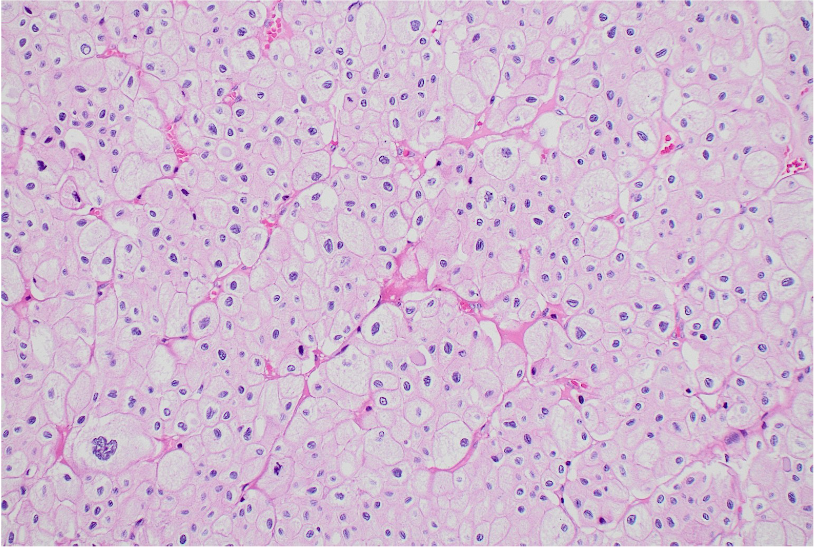

Paciente mujer de 43 años, G0-P000 con antecedentes de hipertensión arterial en tratamiento e historia familiar de cáncer (carcinoma de células de Merkel). Acude por presentar dolor punzante en flanco izquierdo de una semana de evolución. Al examen físico, se palpa masa abdominal móvil y dolorosa. La TC abdominal revela masa sólida ovoidea, de bordes definidos y aspecto encapsulado que mide 139 x 105 mm, asociada a áreas quísticas (Fig 1). Ante estos hallazgos, se realiza nefrectomía radical izquierda. Con la intención de tomar decisiones clínicas inmediatas, se realiza impronta del tumor renal en pieza operatoria observándose células tumorales poligonales con abundante citoplasma eosinofílico granular, membrana citoplasmática bien definida y bordes celulares acentuados. El resultado fue neoplasia de tipo oncocítica que favorece carcinoma cromófobo (Fig 2-5), confirmado histológicamente (Fig 6). Paciente evoluciona favorablemente.

El carcinoma cromófobo de células renales presenta rasgos citológicos característicos, como células poligonales con citoplasma abundante eosinofílico o reticular y membranas celulares bien definidas. Sin embargo, hallazgos clásicos como los halos perinucleares y núcleos arrugados pueden no ser tan evidentes, como en nuestro caso, generando solapamiento con el oncocitoma, principal diagnostico diferencial, que muestra mayor monotonía celular y citoplasma homogéneo, sin reticulación ni vacuolización.3